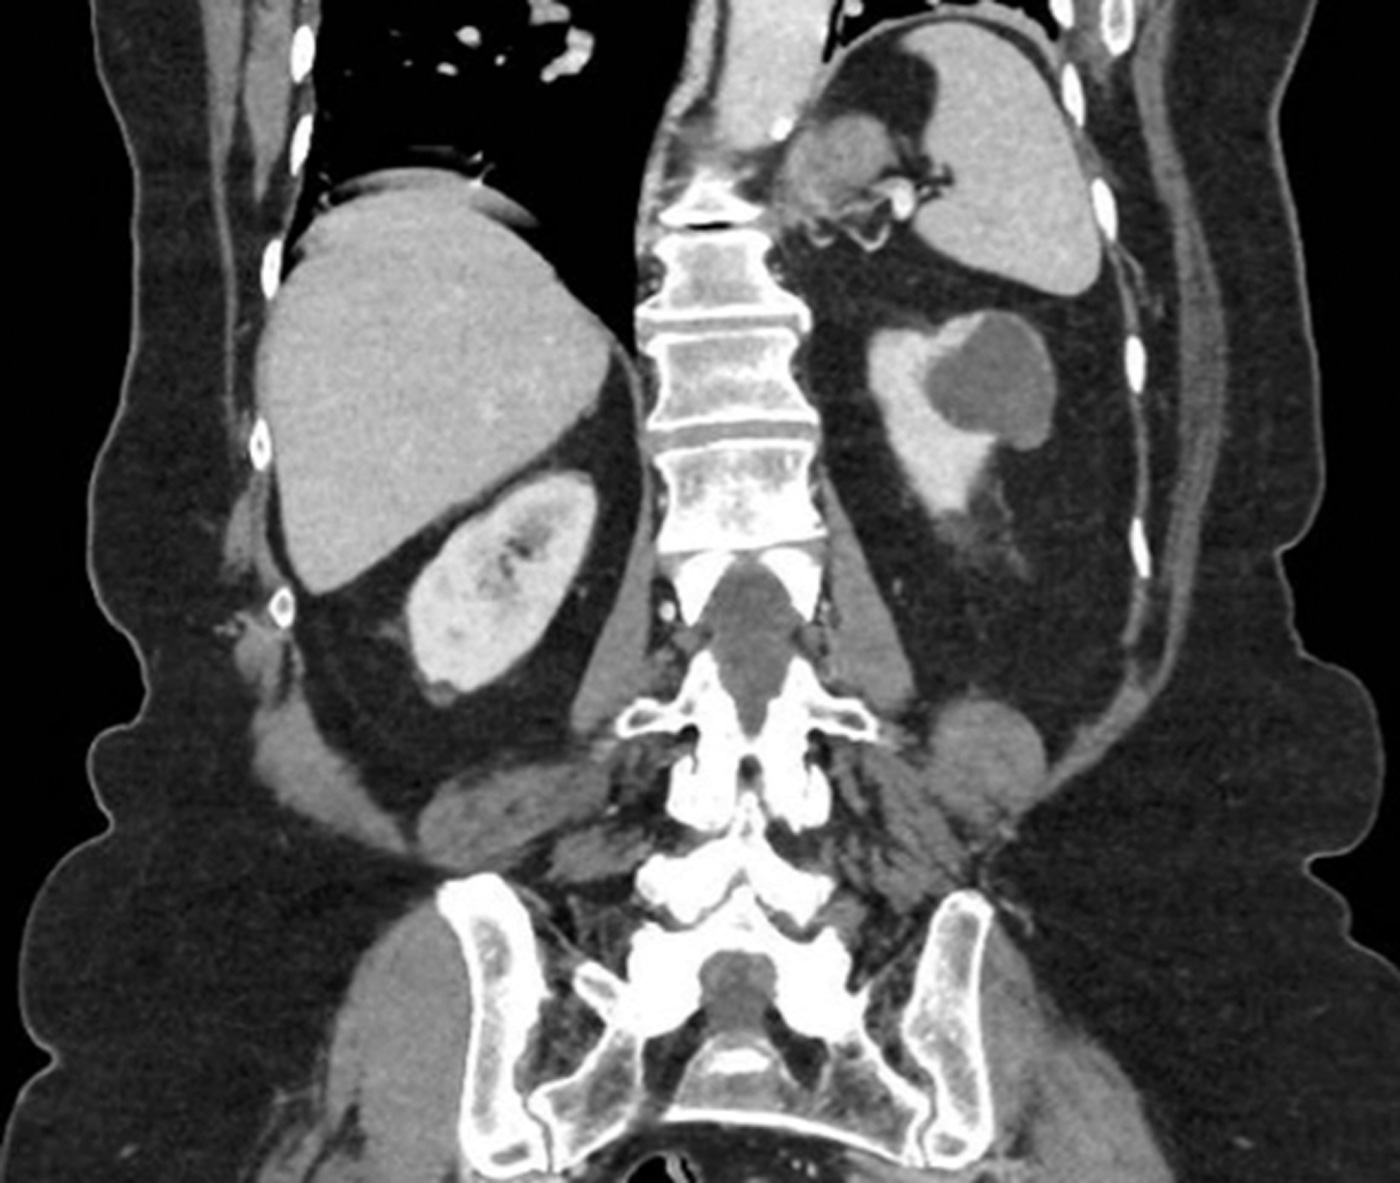

Case 2

A 65-year-old gentleman presented with visible haematuria and underwent the below CT scan. He has hypertension and hyperthyroidism.

Figure 2.

Figure 3.

- What do Figures 2 and 3 demonstrate? What is the stage of this lesion?

1. CT renal consists of multiple phases as outlined below [8]: Non-contrast phase - This is conducted prior to intravenous (IV) contrast administration, with the purpose of detecting calcifications (e.g., renal or ureteric stones) and identifying fat content in mass lesions (e.g., AML). It is also useful in having a baseline attenuation with which to compare the contrast images.Corticomedullary phase - This is conducted approximately 25-40 seconds after contrast injection. Its purpose is to highlight renal arteries, cortex and medulla (the renal cortex enhances preferentially). It is useful in assessing vascular anatomy which can aid surgical planning, and in demonstrating renal artery stenosis / arteriovenous malformations and other abnormalities. It can identify early enhancement in hypervascular tumours.Nephrogenic phase - This is conducted approximately 80-120 seconds after contrast injection. It allows both enhancement of the cortex and medulla and is the best phase for detecting renal masses.

2. This is a 5cm, exophytic, cystic, superior pole tumour of the left kidney, stage T1b N0 Mx.